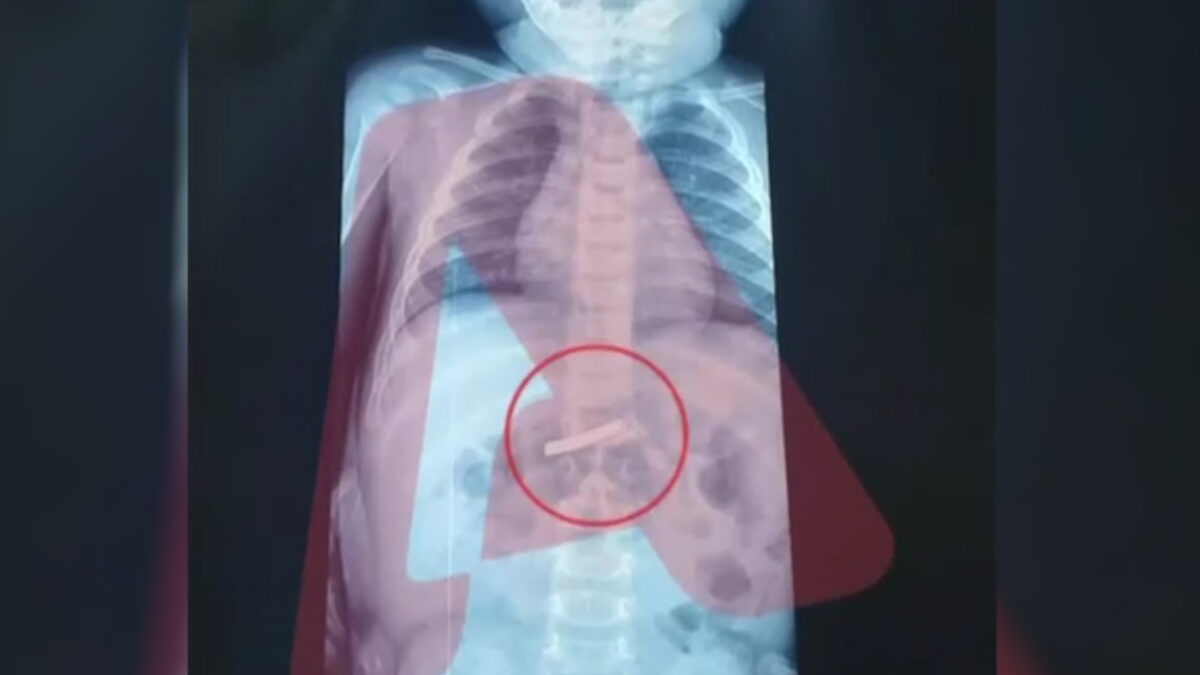

Αμέσως μετά την άφιξή του, το παιδί υποβλήθηκε σε ακτινογραφία, η οποία επιβεβαίωσε την παρουσία του αιχμηρού αντικειμένου στο στομάχι του, προκαλώντας έντονη ανησυχία στο ιατρικό προσωπικό.

Οι γιατροί ενημέρωσαν τους γονείς ότι, μέσω της ακτινογραφίας, εντοπίστηκε με ακρίβεια το σημείο στο οποίο είχε καταλήξει το ξυραφάκι. Αυτό επέτρεψε στη χειρουργική ομάδα να σχεδιάσει με προσοχή την επέμβαση, ώστε να αφαιρεθεί με ασφάλεια.